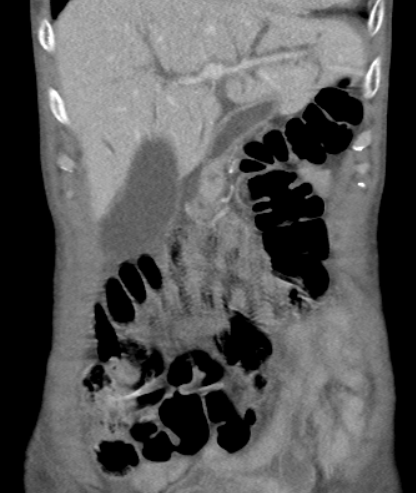

| 복부 X-Ray | 횡행결장 직경 > 6cm, 가스팽창, 장벽 얇아짐 |

| CT | 장벽 비후, 염증 확산, 청공 여부 확인 |